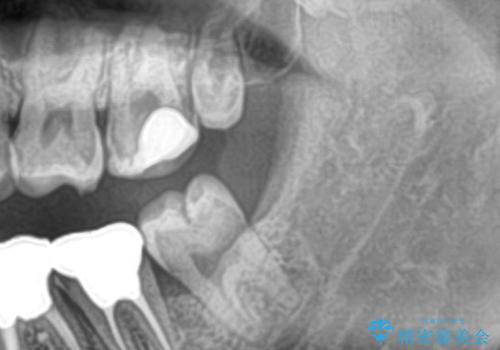

左下の親知らずが腫れた感じがする。

- 左下親知らずが腫れてる感じがして痛いとの事で来院。

抜歯を希望されたので抜歯術を行いました。

親知らずを長年放置すると手前の歯が虫歯になるリスクがあがります。

虫歯になる前に親知らずは抜歯することをお勧めします。